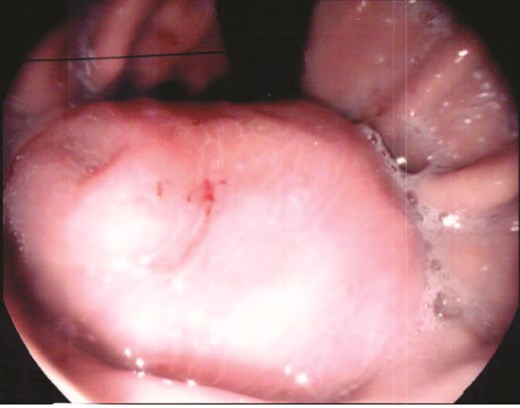

A 70-year-old man initially presented with symptomatic anaemia. Following stabilization, outpatient abdominal computed tomography imaging identified a 10 cm soft tissue mass arising from the gastric fundus. Gastroscopy and biopsy confirmed a GIST (Fig. 1).

Gastroscopy identified a large submucosal mass in the gastric fundus.